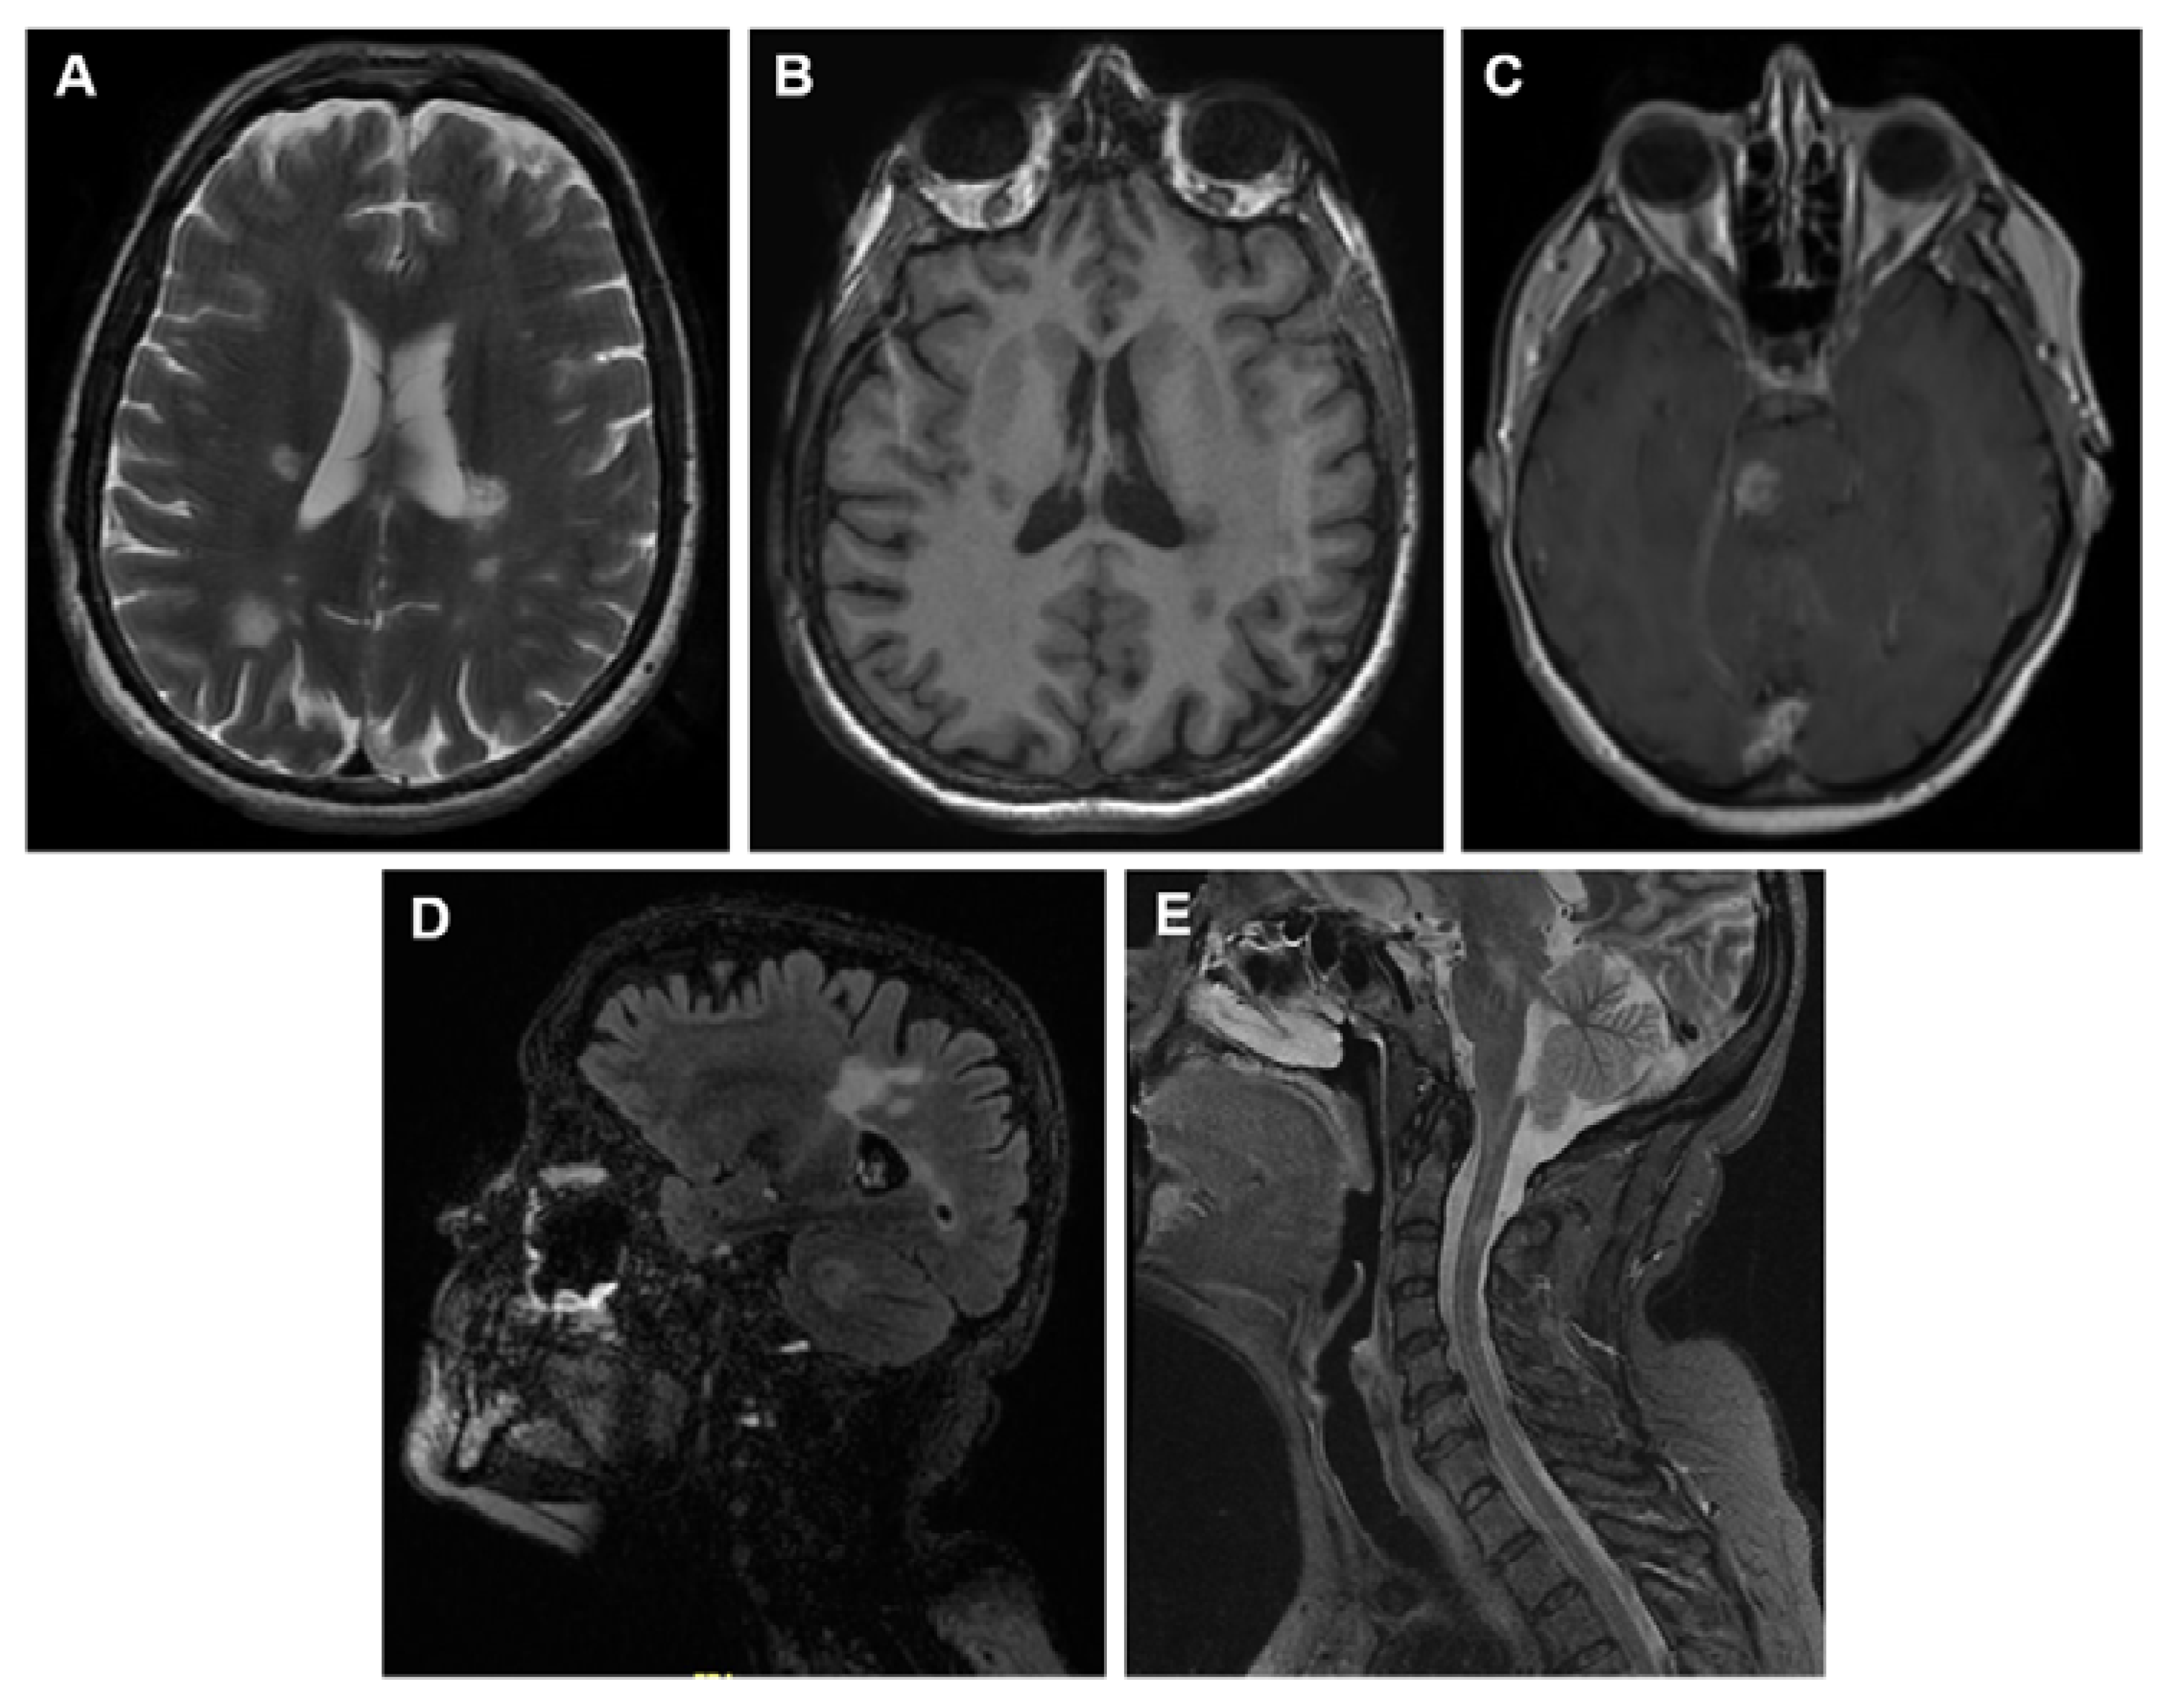

4.2.1. MRI as Diagnostic Biomarker

- T1-weighted or longitudinal magnetization relaxation time;

- T2-weighted or transverse magnetization relaxation time;

- A post-contrast scan. T1-weighted lesions are used primarily to detect any abnormalities in the integrity blood-brain barrier (BBB). Hypointense T1 lesions (also referred to as black holes) are used as a marker representing the loss of axons that occur during the development of MS.

Conventional Image Techniques

- T2- weighted MR imaging

- T1-weighted images with gadolinium enhancement

- Fluid Attenuated Inversion Recovery Sequence (FLAIR)

- Proton density (PD)-weighted spin-echo (SE) images